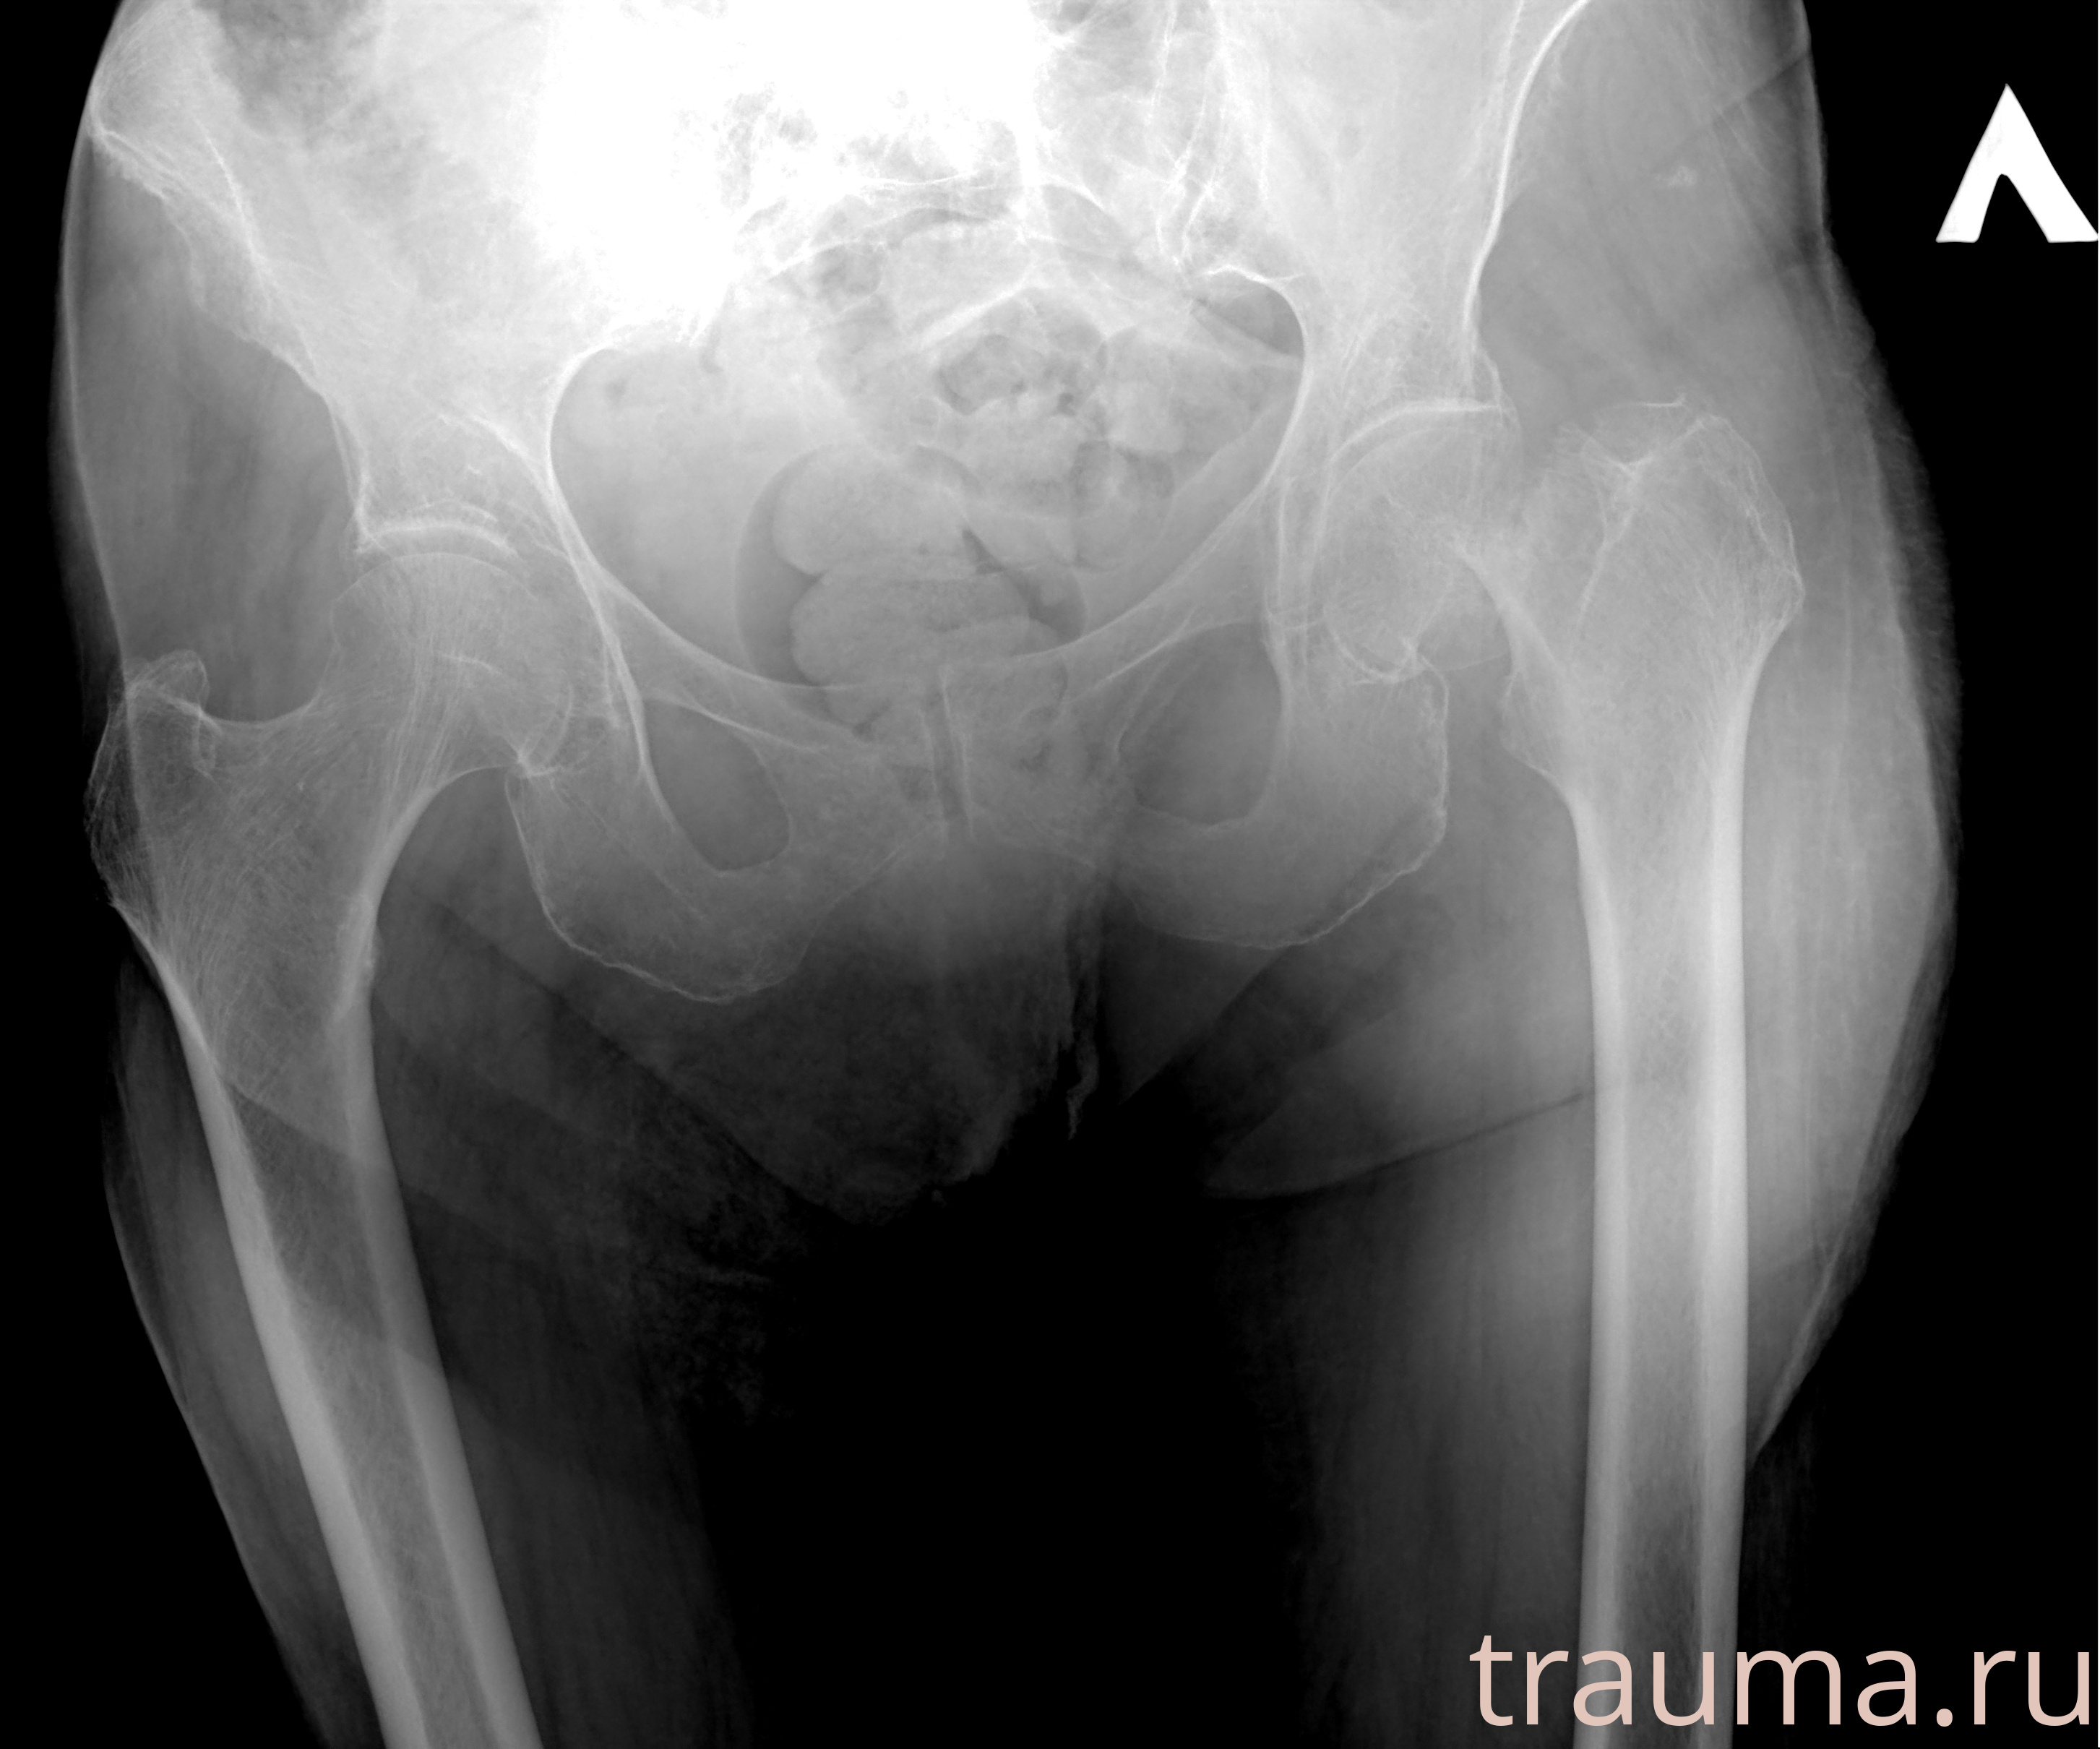

Рентгенограммы

Рентген на дому: по вашему адресу приезжает врач-рентгенолог, травматолог-ортопед с мобильным рентгеновским аппаратом, проводит диагностику травмы или заболевания, делает необходимые рентгенограммы, дает рекомендации по дальнейшему лечению. Получить качественные снимки в домашних условиях возможно благодаря уникальной методике, разработанной МосРентген Центром для института  Склифосовского